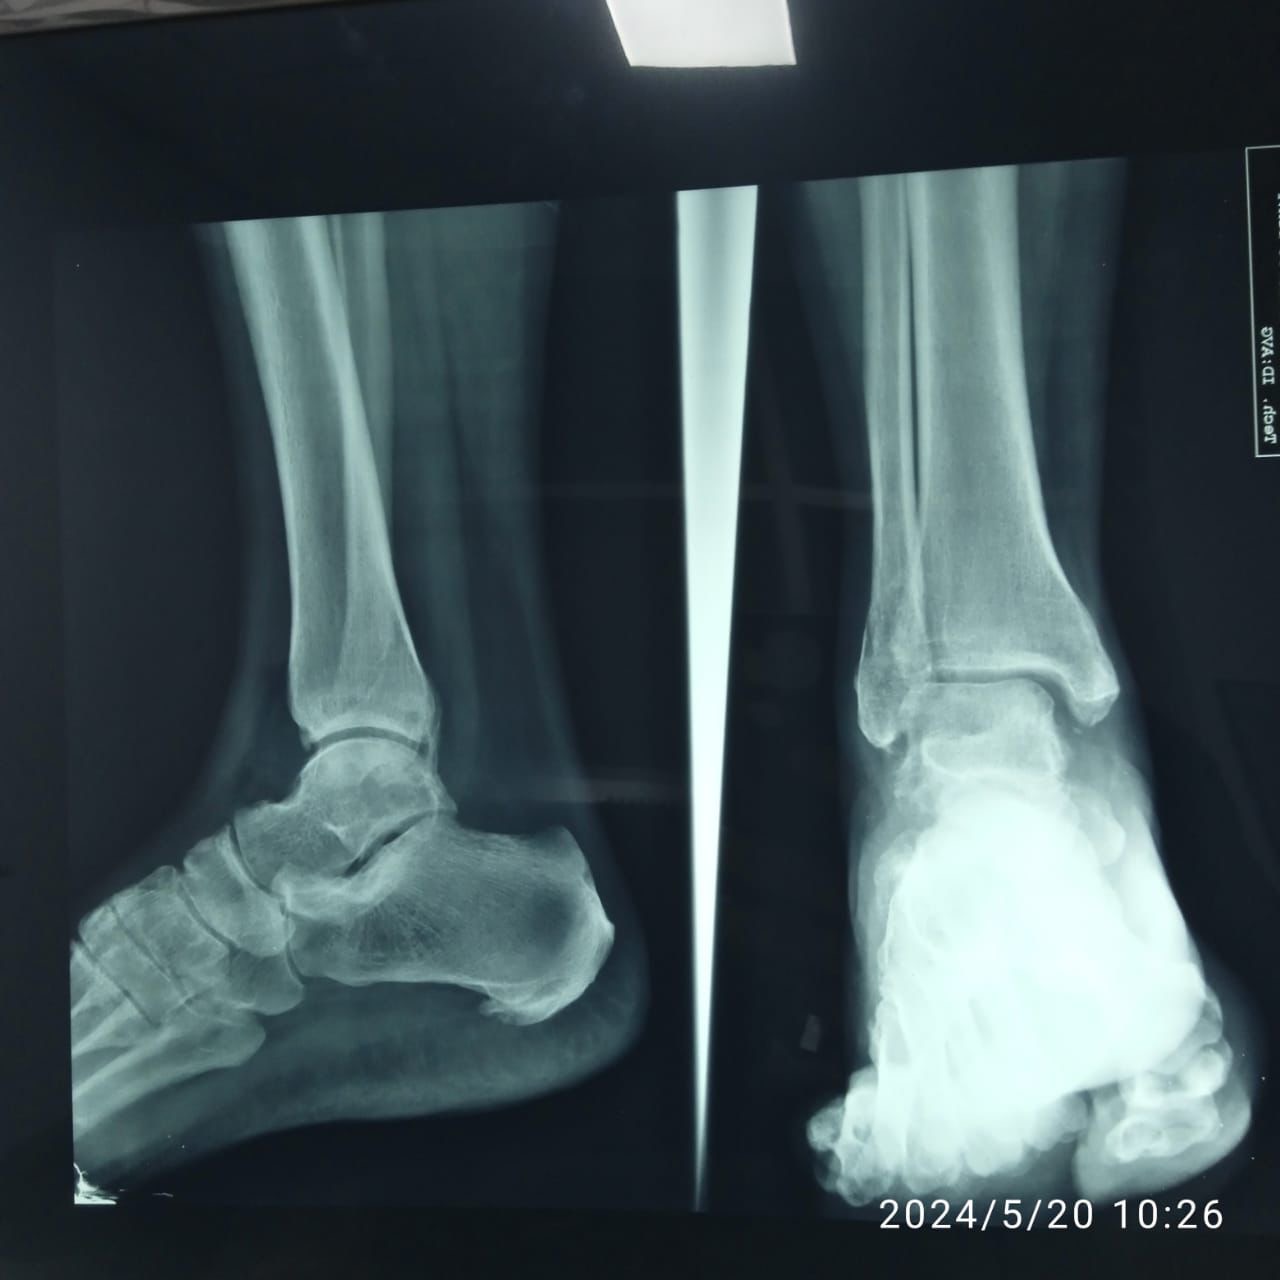

Yoli sufrió una fractura en uno de sus pies tras un accidente en el tren. Actualmente, ella y su esposo venden mangos en los mercados de la Oaxaca y Benito para sobrevivir.

El accidente ocurrió cuando uno de los pies de Yoli quedó atrapado en el tren durante un largo periodo. A pesar de los esfuerzos de su marido, Roberto, para liberarla, no fue hasta llegar a Irapuato que recibieron el apoyo necesario. Al descender del tren en la estación de la ciudad, empleados de Ferromex les brindaron primeros auxilios y facilitaron el traslado de Yoli a un hospital.

El lunes pasado, Yoli acudió nuevamente en compañía de su esposo al médico y recibió la buena noticia de que su hueso ya había sanado y no requería operación. Con esta esperanza, la pareja planea continuar su viaje hacia Estados Unidos en julio o agosto.